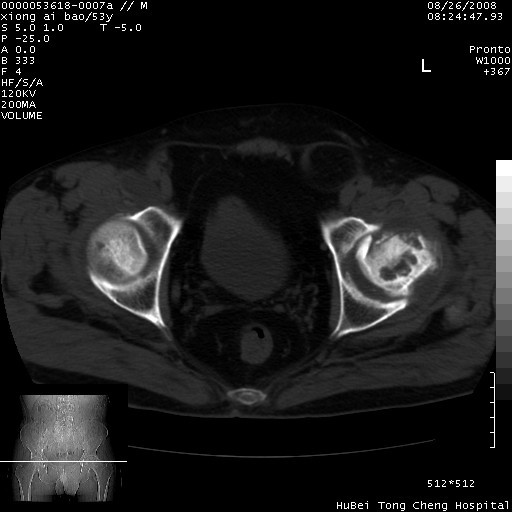

标题: CT15583:M,53Y。请老师指教分析骨盆及其他病变。 [打印本页]

标题: CT15583:M,53Y。请老师指教分析骨盆及其他病变。

股骨头坏死/腹股沟疝。

双侧股骨头无菌坏死,左侧腹股沟斜疝。

非常典型病例,双侧股骨头坏死伴双髋关节周围软组织肿胀,左腹股沟疝。

双侧股骨头坏死伴双髋关节周围软组织肿胀,左腹股沟疝。

双侧骨股头无菌性坏死,左侧腹股沟疝

双侧髋关节肿胀明显,感觉还不能排除结核。

考虑双侧髋关节结核,左侧腹股沟疝